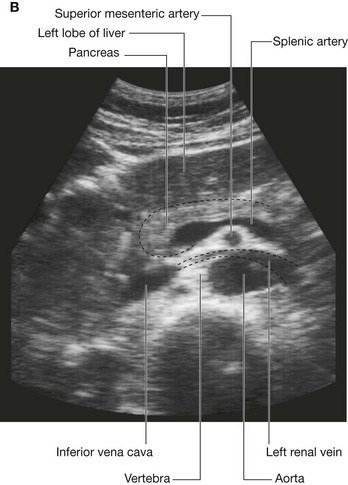

Venous shunts from left to right

All blood returning to the heart from regions of the body other than the lungs flows into the right atrium of the heart. The inferior vena cava is the major systemic vein in the abdomen and drains this region together with the pelvis, perineum, and both lower limbs (Fig. 4.18).

Fig. 4.18 Left to right venous shunts.

The inferior vena cava lies to the right of the vertebral column and penetrates the central tendon of the diaphragm at approximately vertebral level TVIII. A number of large vessels cross the midline to deliver blood from the left side of the body to the inferior vena cava.

image One of the most significant is the left renal vein, which drains the kidney, suprarenal gland, and gonad on the same side.

image Another is the left common iliac vein, which crosses the midline at approximately vertebral level LV to join with its partner on the right to form the inferior vena cava. These veins drain the lower limbs, the pelvis, the perineum, and parts of the abdominal wall.

Page 265

image Other vessels crossing the midline include the left lumbar veins, which drain the back and posterior abdominal wall on the left side.